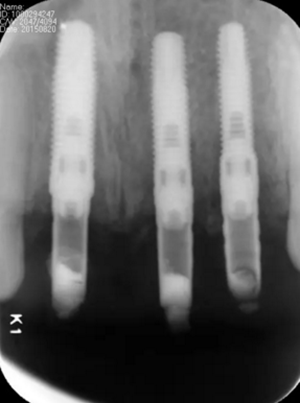

圖3 術(shù)前CBCT

圖13 術(shù)后即刻根尖片

圖17 術(shù)后6個月根尖片

圖24 最終修復(fù)后即刻根尖片